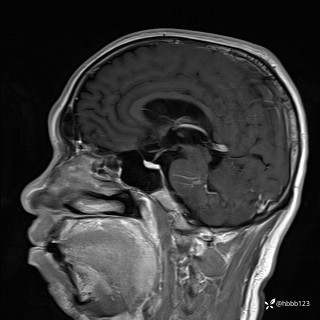

患者男,51岁。

简要病史:患者自述于1周前至某人民医院发现脑干肿瘤(具体不详),为求进一步诊断至我院就诊。

完善颅脑MRI平扫+增强,颅脑CT平扫:

T1增强矢状位重建: